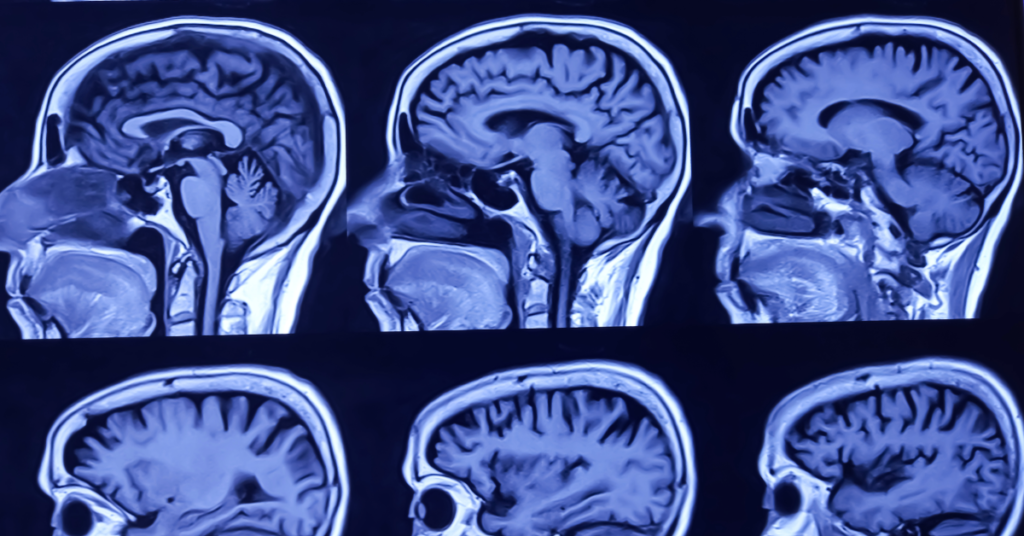

Anestesia e Traumatismo Cranioencefálico: Manejo e Cuidados Primordiais

Introdução ao Cenário de Anestesia e Traumatismo Cranioencefálico O traumatismo cranioencefálico (TCE) consiste em uma lesão que acomete o encéfalo em decorrência de trauma físico, seja por acidentes de trânsito, quedas, agressões ou outros mecanismos de alta energia. A severidade do TCE varia desde contusões cerebrais leves até danos difusos e edema intracraniano extenso, implicando […]